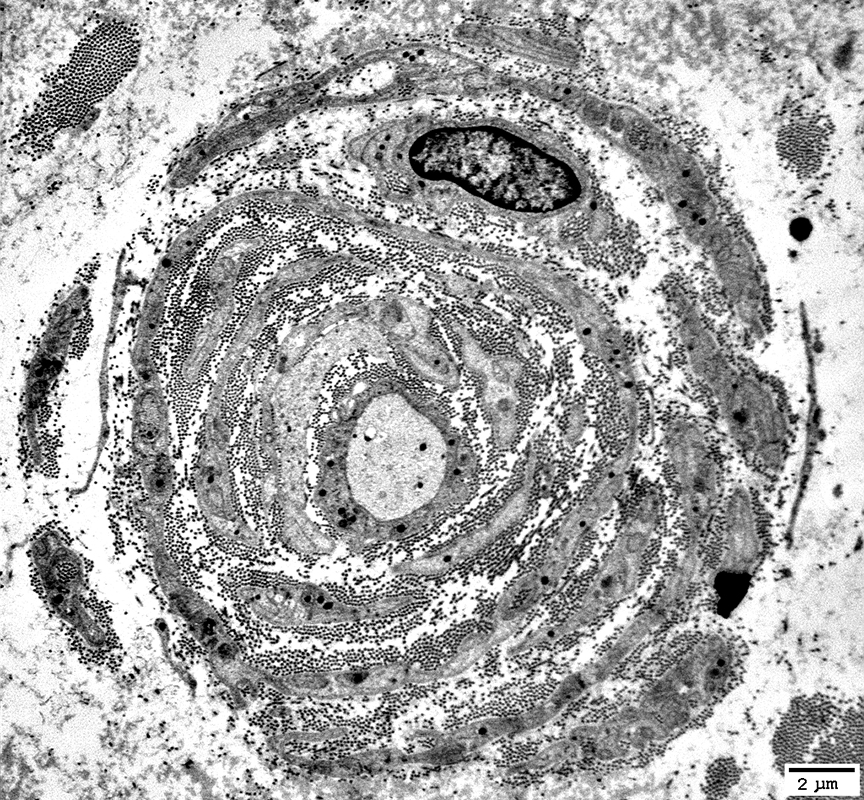

Electron micrograph: From Robert Schmidt MD

Onion Bulbs: Circumferential Layer Components

Schwann cell processes

Schwann cell basal lamina

Collagen: Between Schwann cell components

Fibroblast processes: May form outer layer

Axons in Onion Bulbs

General location: Central

Sizes: Large or Intermediate

Absent: See obsolete onion bulbs

Myelination: Varied

Normal

Thin or Abnormal

None